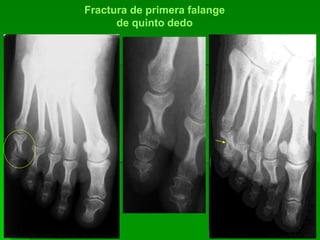

Fractura 1ª falange de quinto dedo izquierdo

Fractura de primera falange

de quinto dedo